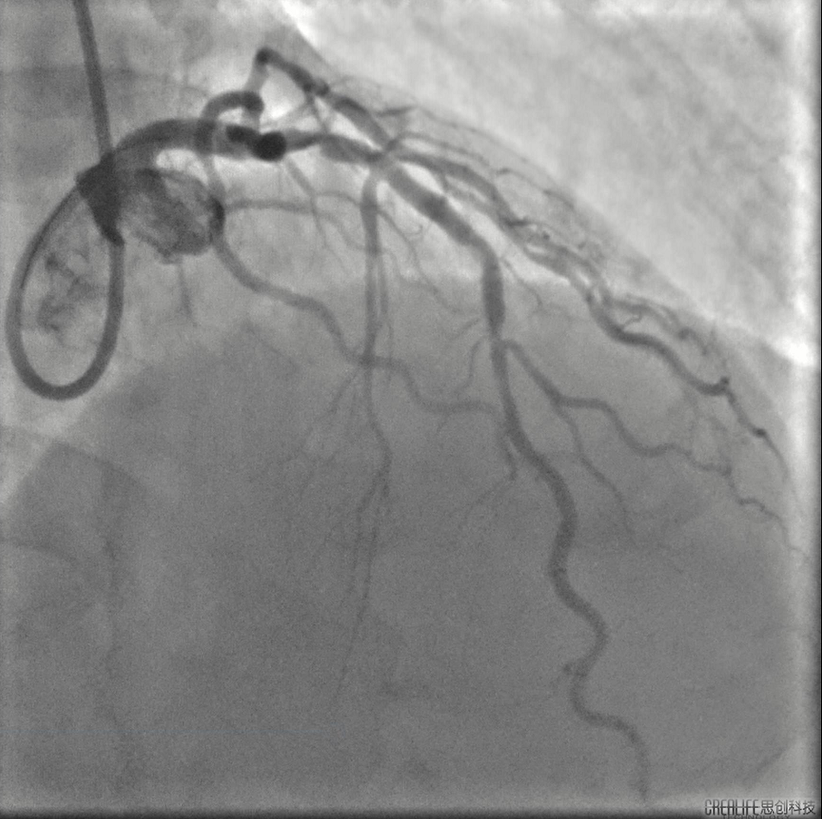

胡洵教授:术前Oct可见前降支中远段严重钙化病变,部分节段呈360度钙化环,最大钙化厚度0.8 mm,中段原支架最小支架面积3.9mm2,支架膨胀率63%,支架外可见明显钙化斑块,近段已用3.0shockwave冲击波球囊进行30次脉冲冲击,钙化病变处可见多处断裂,最深断裂处可达 0.55mm,使用3.0shockwave球囊于中段原支架膨胀不良处进行50次脉冲冲击,2.5shockwave球囊于中远段钙化病变处进行30次脉冲冲击,再次复查Oct可见中远段钙化环出现多处断裂,中段原支架膨胀不良处支架面积明显改善,在前降支远段植入2.5支架,中段原支架内予以3.0高压球囊扩张,近段植入3.5支架并用3.5高压球囊扩张,最后复查Oct见远段支架最小面积 4.21mm2,支架膨胀率75%,中段原支架最小支架面积5.08mm2,支架膨胀率75%,近段最小支架面积 10.20mm2,支架膨胀率85%。